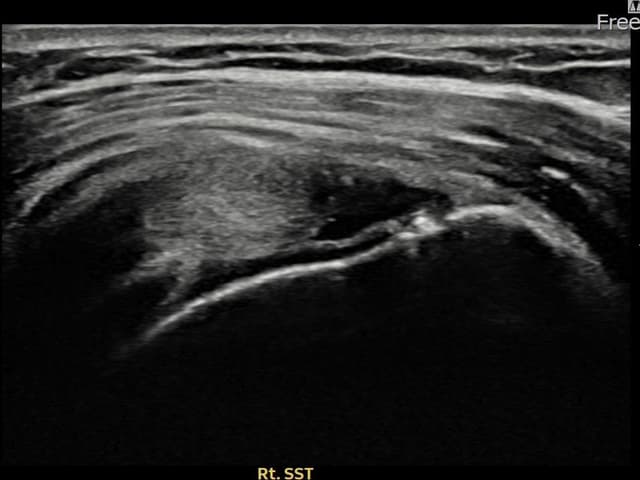

[촬영시기:24.11.04~25.01.14]

[어깨인대 축소봉합술] 좌측 어깨 야간 통증이 심하여 수면에 지장이 있었습니다.